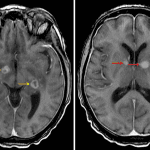

Indication: Confusion in setting of HIV/AIDS

- Multiple enhancing lesions in the bilateral deep gray nuclei and internal capsules, left hippocampal tail, subcortical right frontal lobe, subcortical posterior right temporal lobe, and along the lateral ependymal margin of the frontal horn of the right lateral ventricle

- Several lesions demonstrate central hypoenhancement

- Variable corresponding restricted diffusion

- Surrounding vasogenic edema and local mass effect without midline shift or evidence of herniation or hydrocephalus

Immunodeficiency-associated CNS lymphoma